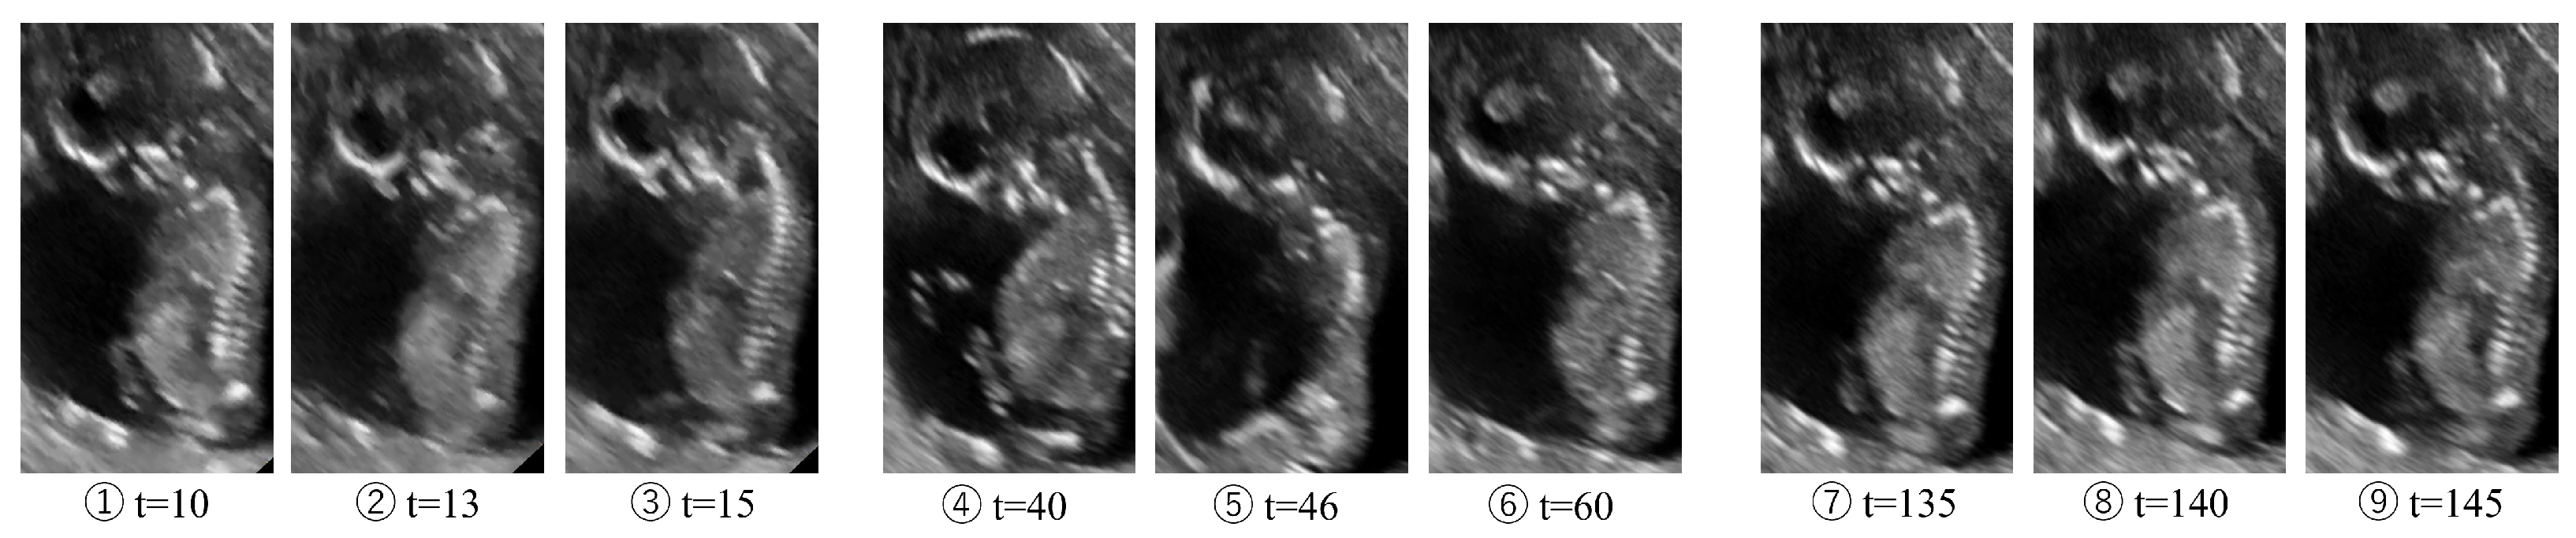

We use a shape description feature to quantify the timing and intensity of fetal movements from the ultrasound video. The video dataset used in this application is an ultrasound video where the sagittal plane of the fetus is consistently captured, including forward and backward bending, as shown in Figure 16. The number written at the bottom of each image is the frame number. However, to reduce the influence of background changes caused by the movement of the mother’s fetus itself, the fetal region is cropped using the Oriented Bounding Box (OBB) in YoLo v8. Furthermore, only the center coordinates and angle of the bounding box are updated based on the predetermined image size to ensure that the image size does not change from frame to frame. The frame rate was 15 fps with 150 frames. Fetal movements occurred around 10–15 frames, 40–60 frames, and 135–145 frames. The fetus is 20 weeks, the sagittal plane is shown, and the head and torso are large in all frames, with some extremities. We define fetal movement as a change in forward and backward bending and analyze the timing and intensity of fetal movement based on this definition.

Figure 16.

Ultrasound images of frames within the fetal movement onset interval. The variable t represents the frame number in the echo movie.

Magnitude of deformation at scale . The orange area represents the actual event of fetal movement annotated by a human, and the blue line represents the estimated magnitude of the fetal movement. The numbers correspond to the frame numbers in Figure 16.

The results were normalized and subsequently processed using a 0.1 Hz low-pass filter. The orange area in the figure indicates the time of onset of fetal movement. The red horizontal lines in the figure represent values that are 3 standard deviations from the mean of , indicating that data points exceeding these lines lie outside the approximately 99.7% range of the overall distribution. The black dotted line indicates the frame number of the image shown in Figure 16.

In Figure 21, for instance, we observed changes in the value even during time periods not exceeding the red line. This suggests the possibility of detecting time periods corresponding to small deformations (e.g., intra-class movement) that do not involve large inter-class transitions. Such subtle deformations are undetectable by discrete shape discrimination and represent an advantage achieved precisely by calculating the continuous magnitude of deformation.

As shown below, the intensity of the deformation increases near the onset of fetal movement, indicating that the intensity of fetal movement can be estimated. It is also clear that the time of onset of fetal movement can be detected because the timing of the fetal movement can be said to be the timing when the magnitude of the deformation is large. Based on these results, it is clear that shape change recognition can be performed using shape feature vectors. This study was conducted on images in which the shape of the fetus was always visible, but for practical use, features that can be interpolated even if the majority of the fetus is not visible are required.